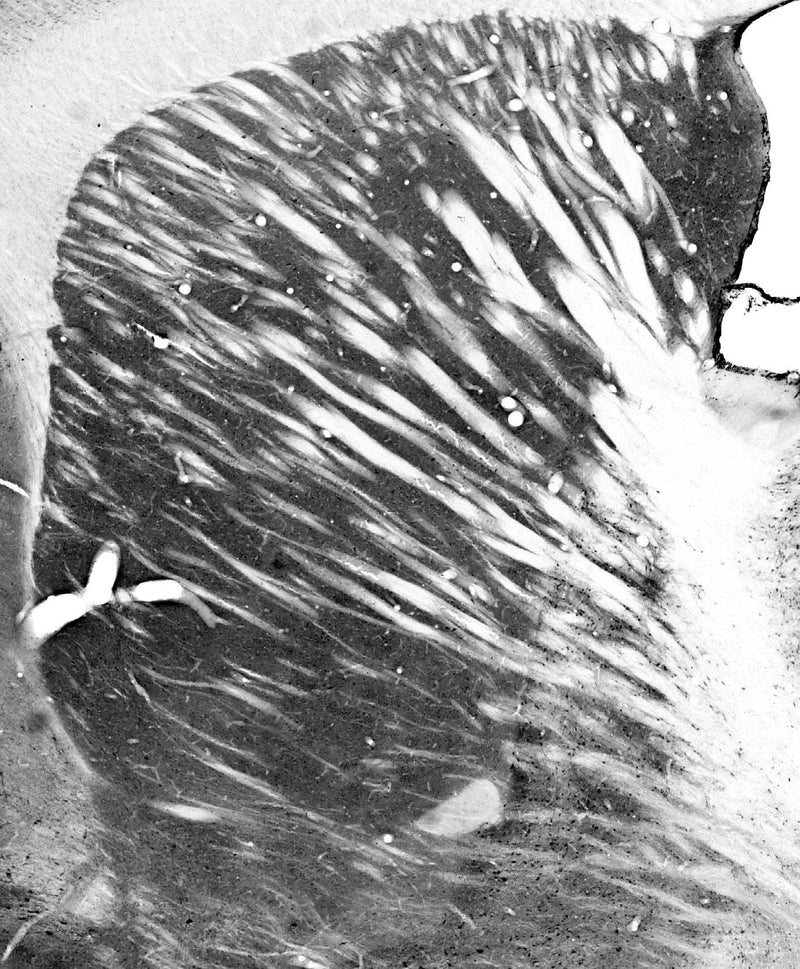

Each new lot of antibody is quality control tested by IHC on either rat or mouse brain and confirmed to give the expected staining pattern.